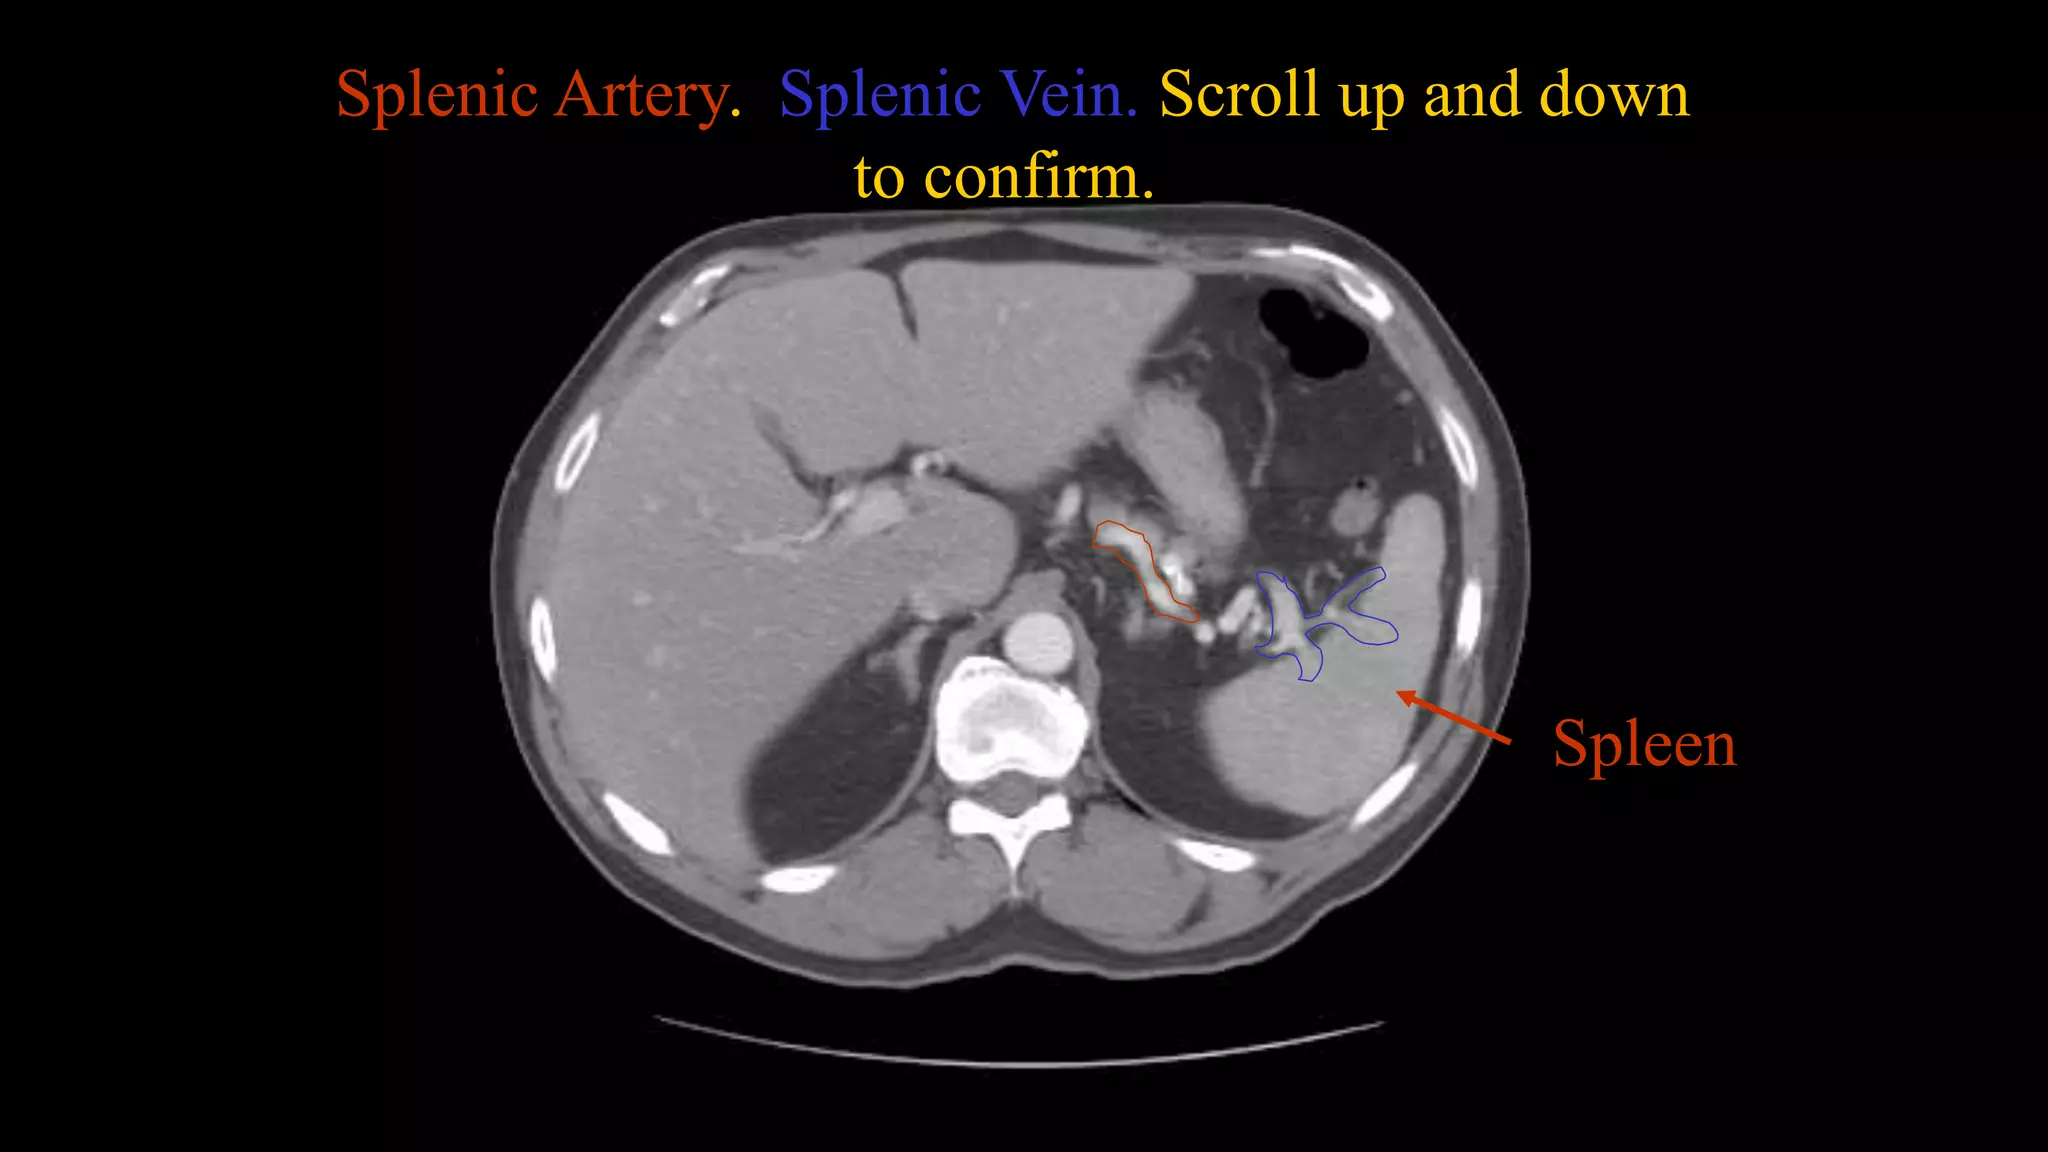

Splenic Artery. Splenic Vein. Scroll up and down

to confirm.

Spleen

Splenic Vein

Splenic Artery. SplenicVein. Scroll up and down to confirm. Spleen

• 24.